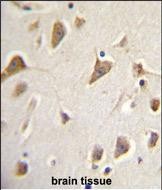

| IHC | 1/100-1/500 | Human,Mouse,Rat |

Antibodies against ZMYND10 are widely used in research to assess protein expression and localization via techniques like Western blotting, immunohistochemistry, and immunofluorescence. They help elucidate its role in cancer biology and its potential as a diagnostic or prognostic biomarker. Additionally, ZMYND10 has been linked to ciliary function, with mutations causing primary ciliary dyskinesia, highlighting its broader physiological relevance. The antibody thus serves as a critical reagent in both oncological and developmental studies.